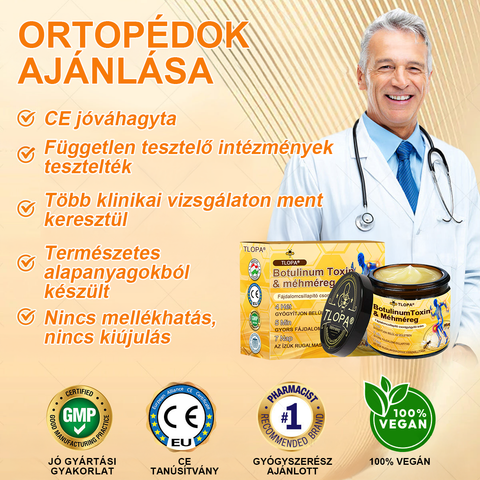

TLOPA® Botulinum Toxin és Méhméreg Fájdalomcsillapító Csontgyógyító Krém

a Magyar Ortopéd Társaság (MOT) által tanúsított és ajánlott termék, amely megfelel a magas szabványoknak a fájdalom hatékony enyhítésére és a csontok egészségének elősegítésére. Az ortopéd orvosok által jóváhagyott, 5 percen belül enyhíti a fájdalmat, 7 nap alatt visszaállítja az ízületi mozgékonyságot, és 4 héten belül jelentősen javítja az arthritis tüneteit. Válassza a Botulinum Toxin és Méhméreg Fájdalomcsillapító Csontgyógyító Krémet, és élvezze a megbízható eredményeket és a kellemes élményt bizalommal.

✓ Enyhíti az ízületi gyulladást és fájdalmat

✓ Eltávolítja a cisztákat és ödémát

✓ Elősegíti az ízületi szövetek regenerálódását, javítja az ízületi rugalmasságot és mozgékonyságot

✓ Elősegíti az ízületek helyreállítását és regenerációját

✓ Elősegíti a vérkeringést

✓ Nincs mellékhatása

✓ Nappal és éjszaka egyaránt használható

✓ Hatékony egy alkalmazás után

✓ Klinikailag igazolt hatékonyság

✓ A TLOPA® fejlesztette és gyártotta, TGA jóváhagyással

✓ Nem tartalmaz káros összetevőket

✓ Állatkísérlet-mentes

✓ Ortopéd orvosi szakértők ajánlásával